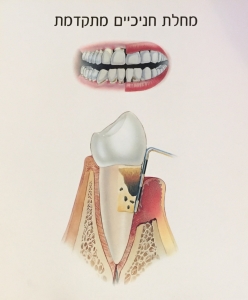

"סרגלון" דמוי מחט נכנס לאזור הכיס שבין השן לחניכיים ובעומק של מעל ל- 2 מילמטר מראה על מחלה.

"סרגלון" נכנס לעומק הכיס ומצביע על מחלת חניכיים מתקדמת.

בדרך כלל רופא החניכיים ולעיתים גם השיננית מבצעים בדיקה עם "הסרגלון" ורושמים בטבלה את עומק הכיסים ועל סמך המדידות קובעים את הטיפול המתאים

פריודונטיטיס – השלב שבו ישנה התפתחות של הדלקת לכרונית ותגובת נגד של המערכת החיסונית כנגד רכיבי הגוף עצמו.

כתוצאה מכך נגרם הרס נרחב של החניכיים ושל רקמת העצם התומכת בשן במקרה של פגיעה בעצם המצב אינו הפיך אך ניתן לעצירה בטיפול מתאים ובשמירה על היגיינה תקינה כך שהמצב לא יחמיר.

מחלת חניכיים נרחבת – בשלב זה מרבית השיניים מיועדות לעקירה.